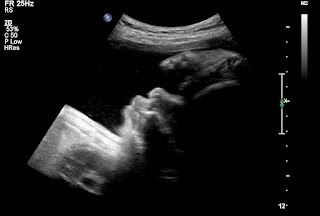

35w6d u/s

Had a good u/s yesterday at 35 weeks and 6 days. Baby B is going to be a bigggggg baby if he makes it all the way until the end of August! Yesterday he was measuring at 6lbs 15oz! Yeah....at just under 36 weeks!

I had an u/s with ds #1 (4.5 years ago) at 36 weeks since my belly was measuring 4 weeks behind. Ds #1 was estimated to be 4lbs 1oz at that time! Quite the difference!

The u/s tech said that if Baby B makes it to his due date, she thinks he will be around 9lbs. Guess we will just have to wait and see!

And for fun.... here is a pic of ds #1 @ 36 weeks